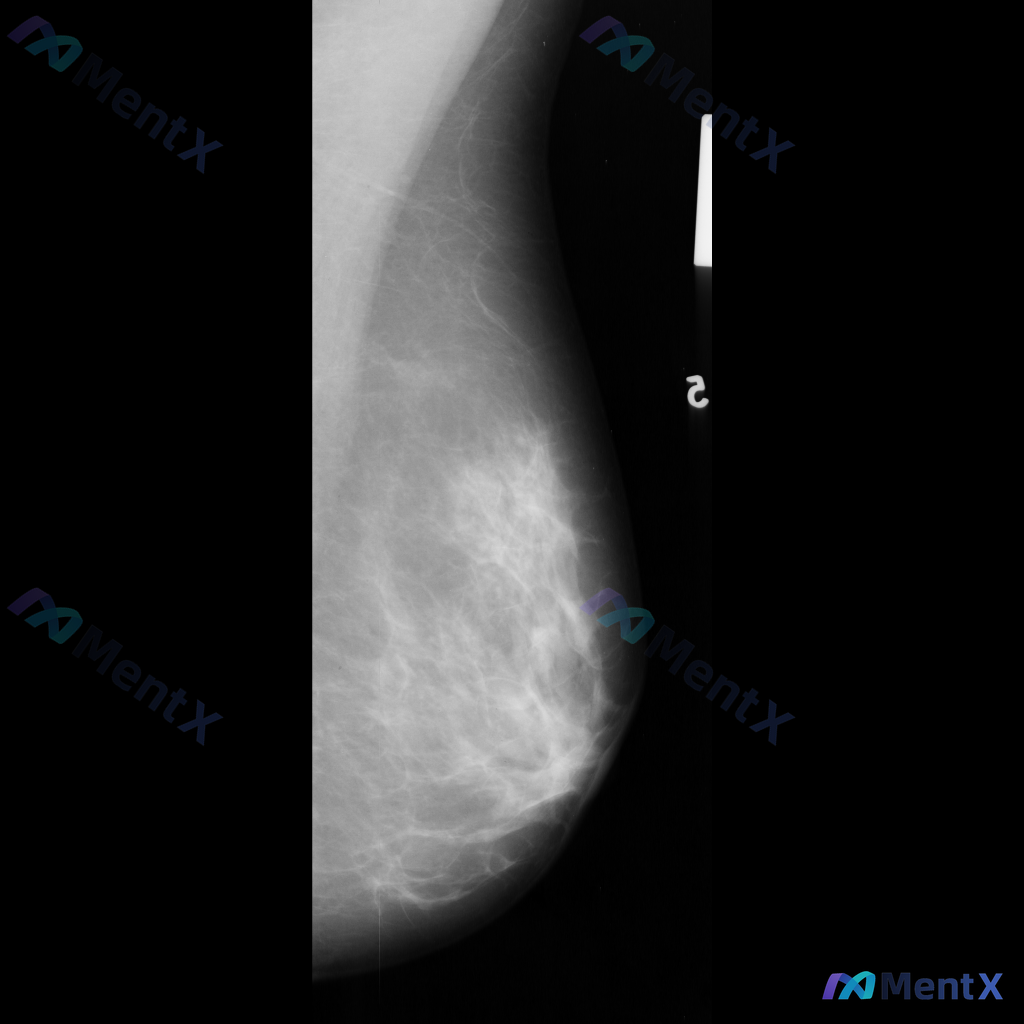

左侧乳腺钼靶MLO位影像:这处异常最应该优先考虑哪种方向?

- 影像类型:左侧乳腺钼靶内外斜位(MLO)

- 左侧乳腺中上部及外侧可见局灶性结构扭曲

- 乳腺腺体组织以纤维腺体为主,密度较高,为不均匀致密型(ACR BI-RADS C型)

- 腺体可见多发斑片状、结节状高密度影,与周围腺体融合

- 可见散在分布的少许粗大钙化点,形态多为良性

BI-RADS 0类,提示需要召回进一步检查。